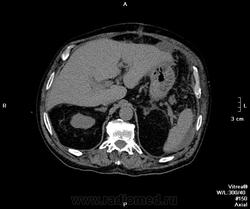

Пациент поступил ко мне через 6 дней после ушивания перфоративной язвы ДПК. УЗИ-сты увидели инфильтративно-жидкостные изменения в зоне оперативного вмешательства, пузырьки газа. Но смутило найденное образование в пространстве между правой долей печени и паранефрием. цель исследования - дифференцировать найденное между инфильтрацией и жидкостным скоплением.

Пациента готовили в течение 2 часов, перорально разведенный урографинчик дробно, и пол станканчика перед исследованием (это важно). Болюс в артериальную и венозную фазы.

- меня смущает не типичный вид артериальной фазы, и уж тем более венозной

Усиление коркового вещества слабое, задержка начала нефрографической фазы. диаметр почечным артерий около 5 мм, почечных вен -- 10мм. на 60 секунде отсутствует должное конрастирование вен, без признаков патологического сброса

Случай 1. Атеросклероз сосудов, запаздывание фаз секунд на 20-25. Получили раннюю артериальную фазу (посмотрите контрастирование камер сердца). И вместо портальной - нечто между поздней артериальной и портальной. Стоило, как мне кажется, сделать 85-90 сек, тогда бы попали в порталку.

По поводу жидкостей в брюшной полости (инфильтраты? где? Виталий показывает скопление жидкости у левой венечной связки) - нормальное послеоперационное их распределение, результат самой операции - т.е. лизированная кровь, ничего криминального, в соответствии с анатомией связок (в том числе и левой венечной, селезеночно-ободочной, желудочно-диафрагмальной)), обычная п/о реакция клетчатки. Абсцессов нет.